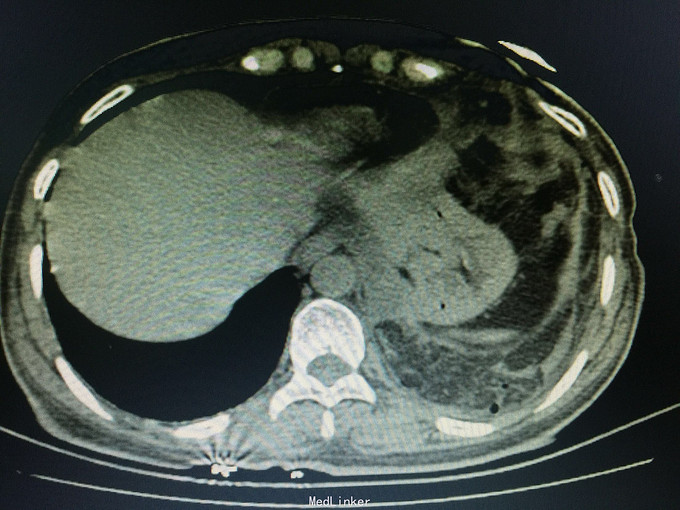

女,41岁, 主诉:腹部胀痛伴不排便、不排气1周, 现病史:一周前无诱因开始腹部胀痛,逐渐加重,以左上腹明显,不排便,不排气,恶心,呕吐数次胃内容物,在当地医院抗炎治疗不见好转,今排腹部平片诊断为“肠梗阻”,来诊。

一般状态可,腹部平坦,未见肠型及蠕动波,脐周压痛,左上腹明显,无腹肌紧张,未及包块,移动性浊音阳性,肠音2次/分。 辅助检查:全腹CT:腹部肠管明显扩张,积液,左侧膈肌局部缺损,腹腔内肠管及系膜组织疝入胸腔。

诊断:膈肌疝,疝内容嵌顿,肠梗阻 处理:手术治疗。